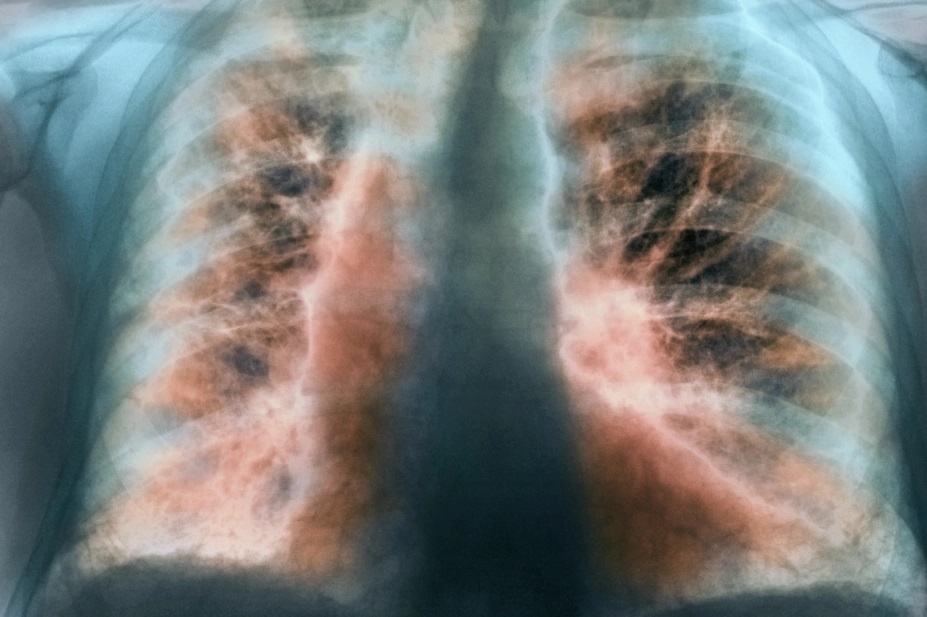

Qua kiểm tra, các bác sĩ đã định hướng đến nguyên nhân co giật của bệnh nhân do hạ canxi máu. Người bệnh ngay lập tức được bù dịch, điện giải. Đồng thời, khi chuyển Khu điều trị hậu Covid-19, Đơn vị Nội yêu cầu, các bác sĩ phát hiện thêm tình trạng khó thở, hụt hơi do tổn thương phổi sau Covid-19, kèm theo rối loạn chức năng tiền đình, rối loạn lo âu, giấc ngủ...

Tại đây, nhân viên y tế tiếp tục bù dịch, điều chỉnh rối loạn điện giải, điều trị tổn thương phổi hậu Covid-19 cho bệnh nhân. Ngoài ra, chị V. cũng được hướng dẫn các bài tập thở, giải quyết rối loạn lo âu, giấc ngủ.

Sau 3 ngày điều trị, bệnh nhân đã hết các rối loạn điện giải, đỡ hụt hơi, khó thở, trở về giấc ngủ sinh lý bình thường.